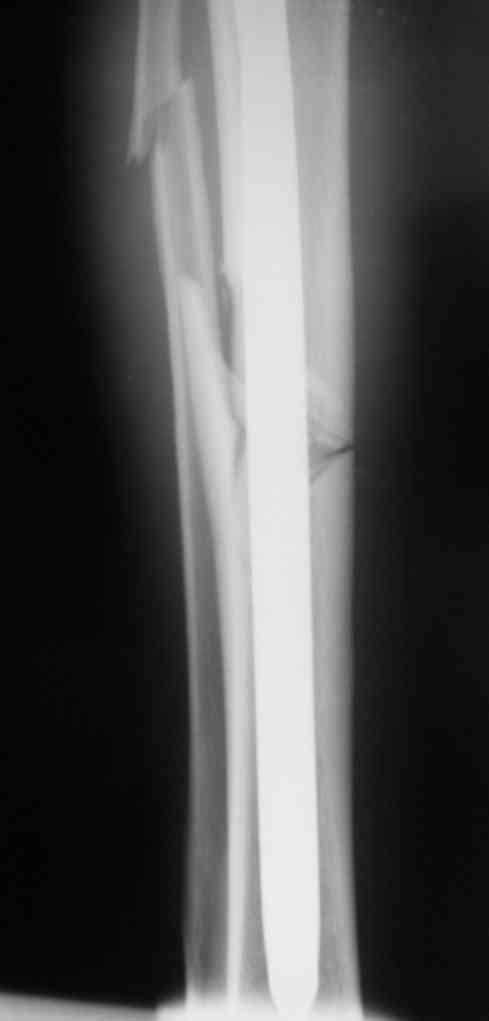

Вчера первый раз синтезировали голень гвоздем Fixion.

Спиральный оскольчатый перелом, ниже середины, у молодого парня. Сделали "классический" вариант гвоздя, который еще без винтов. Получилось все легко. Не торопясь, сделали операцию минут за 20. См. фото.

В отношении ранней нагрузки при спиральных переломах лучше не торопиться. По данному случаю необходимо достигнуть исчезновения щели между штифтом и внутреним кортексом по Rg. А так картинка прекрасная - и длина сегмента и репозиция. Можно поздравить, коллега!